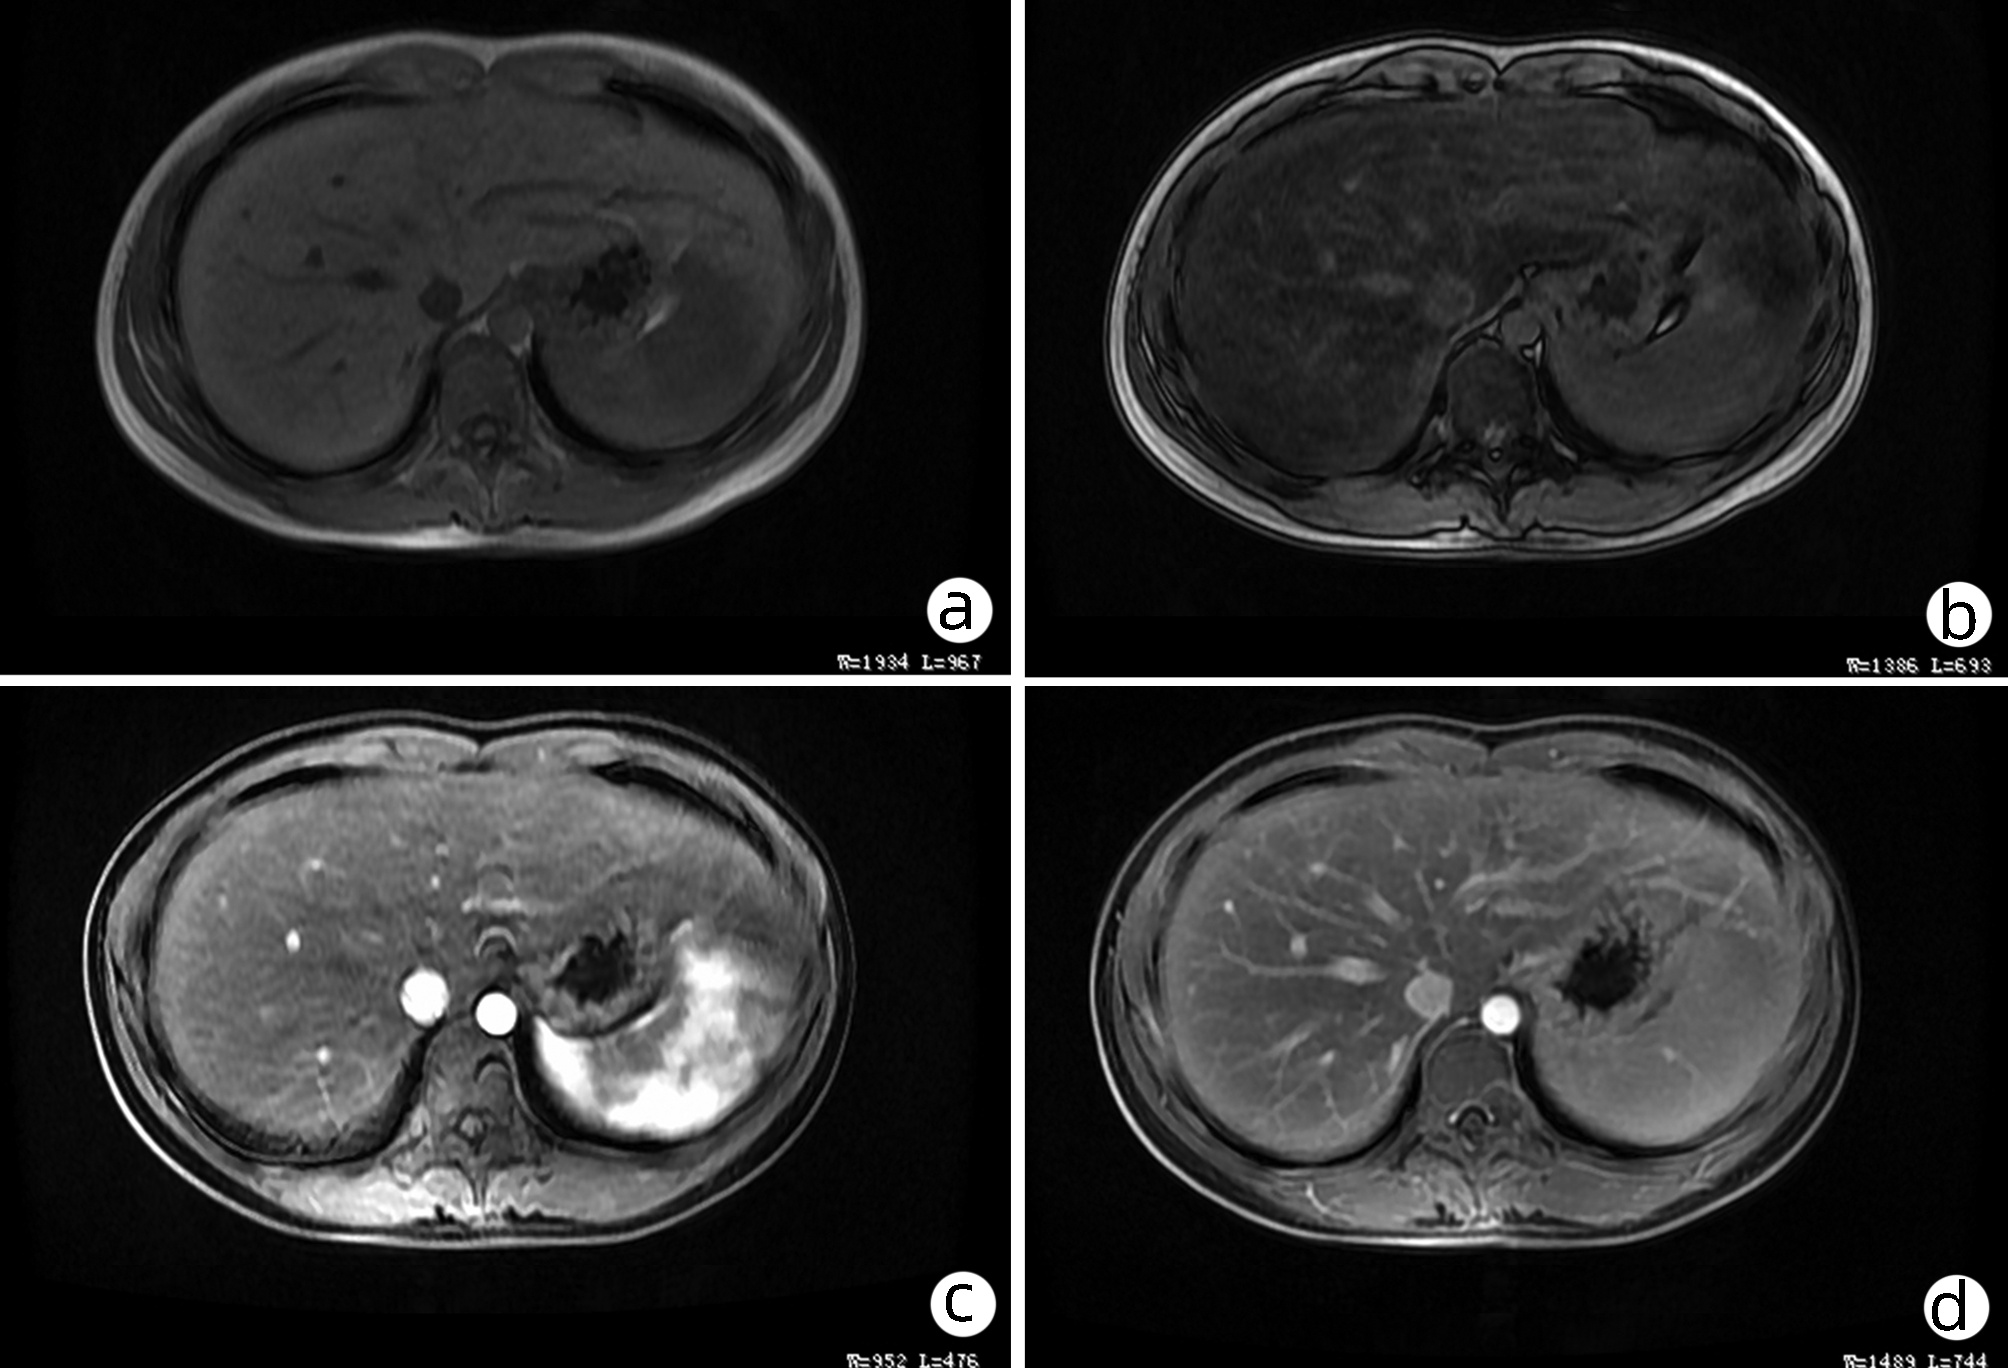

Hepatocellular carcinoma with bile duct tumor thrombus: A case report

Renjie LU, Fangfang SUN, Jie DU, Lirong ZHAO

2022, 38(8): 1872-1874. DOI: 10.3969/j.issn.1001-5256.2022.08.028

Abstract(762) HTML (437) PDF (3665KB)(68)

Abstract: